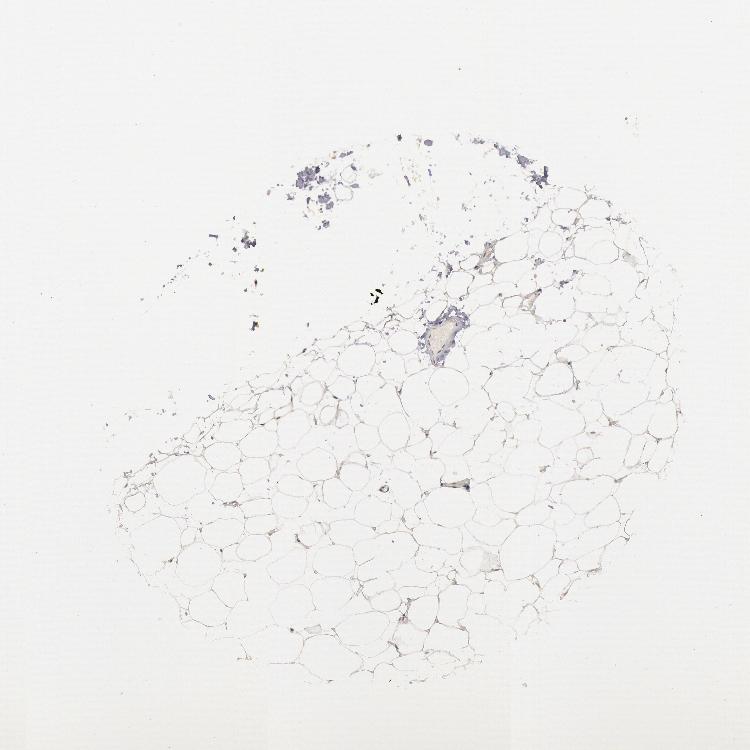

TISSUE PRIMARY DATA SOFT TISSUE Show tissue menu

SOFT TISSUE - Expression summary

SOFT TISSUE 1 - Antibody stainingi

Antibody staining in the annotated cell types in the current human tissue is reported as not detected, low, medium, or high, based on conventional immunohistochemistry profiling in selected tissues. This score is based on the combination of the staining intensity and fraction of stained cells.

Each image is clickable and will lead to virtual microscopy that enables deeper exploration of all samples and also displays staining intensity scores, fraction scores and subcellular localization as well as patient and tissue information for each sample.

Antibody HPA001306Antibody CAB033665

Chondrocytes -High

Fibroblasts Low-

Peripheral nerve Not detected-